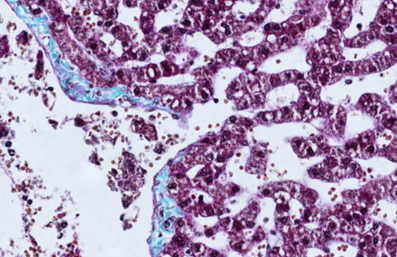

A 55-year-old man presents for a routine checkup

that reveals abnormal liver function tests. Other tests and routine imaging are

not diagnostic, so the patient is sent for a liver biopsy. In addition to

hepatocytes, the sample will also include capillaries through which blood flows

around the vascular poles of hepatocytes. What is typical for these vessels?

View this question